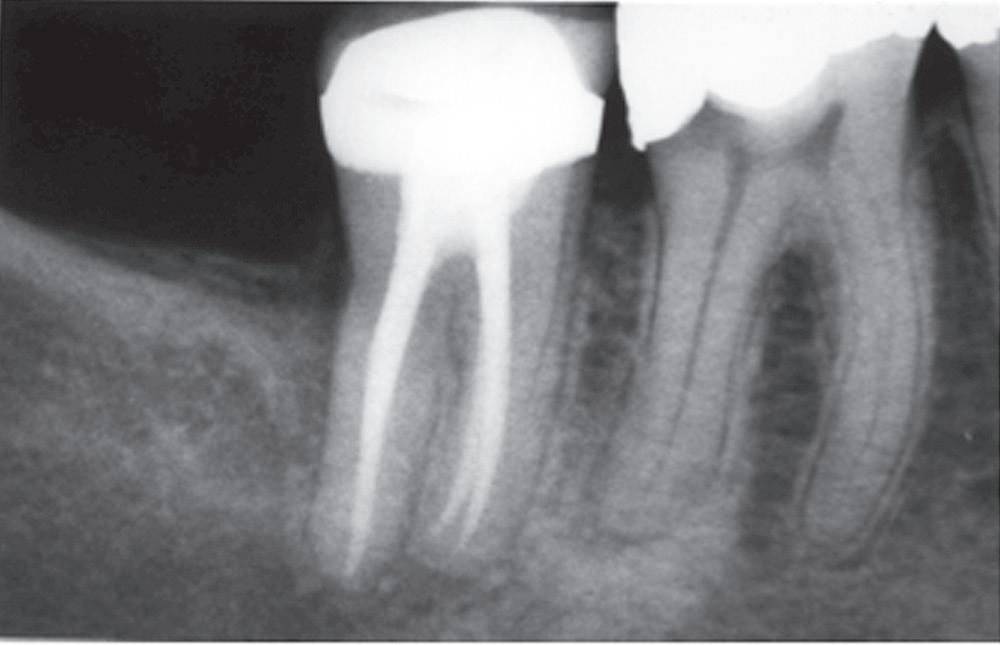

• Fig. 1.9 A, Preoperative radiograph of a second molar with pulpal necrosis and evidence of chronic apical periodontitis. B, Postoperative radiograph of the tooth. C, Postoperative radiograph 2 years after root canal therapy shows complete resolution of the periradicular pathosis.